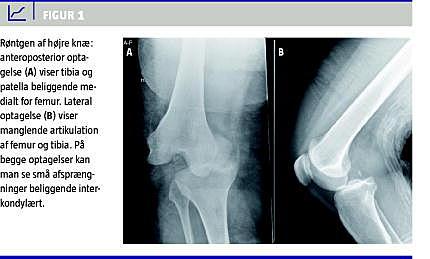

Sygehistorie

En 55-årig kvinde holdt stigen for sin mand under havearbejde. Manden mistede fodfæstet, faldt ned af stigen og landede ovenpå patientens højre knæ. Patienten fik straks stærke smerter i højre knæ, der også »sad underligt«. Patienten indbragtes af Falck med benet lejret på en bunke tæpper. Ved ankomsten konstaterede man en fejlstilling af højre knæ, denne tolkedes i første omgang som en patellaluksation. Ved palpation af knæet konstaterede man, at det var lukseret. De perifere neurovaskulære forhold fandtes -intakte, og patienten blev sendt til røntgenundersøgelse. Røntgen af højre knæ viste medial knæleds-luksation med en lille avulsion beliggende interkondylært (Figur 1 ). Patienten blev indlagt og fik i fuld anæstesi foretaget reposition af knæet. Ved undersøgelse i fuld anæstesi fandtes mistanke om læsion af det laterale kollaterale ligament (LCL), forreste korsbånd (ACL) og det bagerste korsbånd (PCL). Efter reposition var de perifere neurovaskulære forhold normale. Der blev anlagt en gipsskinne med knæet i 30°-fleksion. Arteria poplitea blev fulgt løbende for eventuel intimaskade. Næste dag blev patienten overflyttet til en afdeling, der er specialiseret i behandling af flerligamentskader. Der blev foretaget en magnetisk resonans-skanning, som viste ruptur af LCL og popliteussenen i det proksimale hæfte, total ruptur af ACL og PCL, partiel fascia lata-ruptur og partiel afrivning af det mediale kollaterale ligament proksimalt. Patienten fik 14 dage efter skaden indtraf foretaget rekonstruktion af ACL og PCL, LCL og popliteussenen blev reinsereret, og defekten i fascia lata blev sutureret. Postoperativt fik patienten anlagt en låst hængselbandage, som gradvist blev låst op. Patienten fik specialiseret genoptræning.